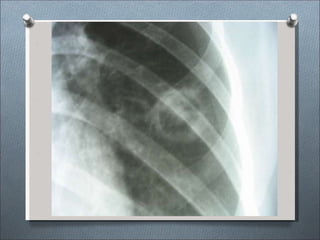

Formas clínicas radiológicas:

•Enfermedad asintomática y tipo gripal.

•Tipo neumónico: Consolidación parenquimal de

lóbulos inferiores.

•Ensanchamiento linfático hiliar o mediastinico.

•Neumotórax.

•Lesiones nodulares con o sin cavitación.

•Lesiones miliares.